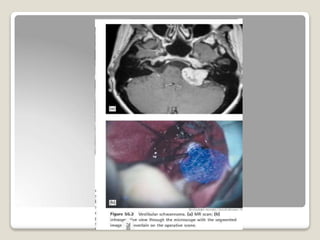

Otology :

• Locating facial nerve

• Identifying lesions of petrous apex

• Tumours of IAC.

• meningiomas

• vestibular schwannomas

• Mastoid surgery

• locate dura ,brain,jugular bulb.